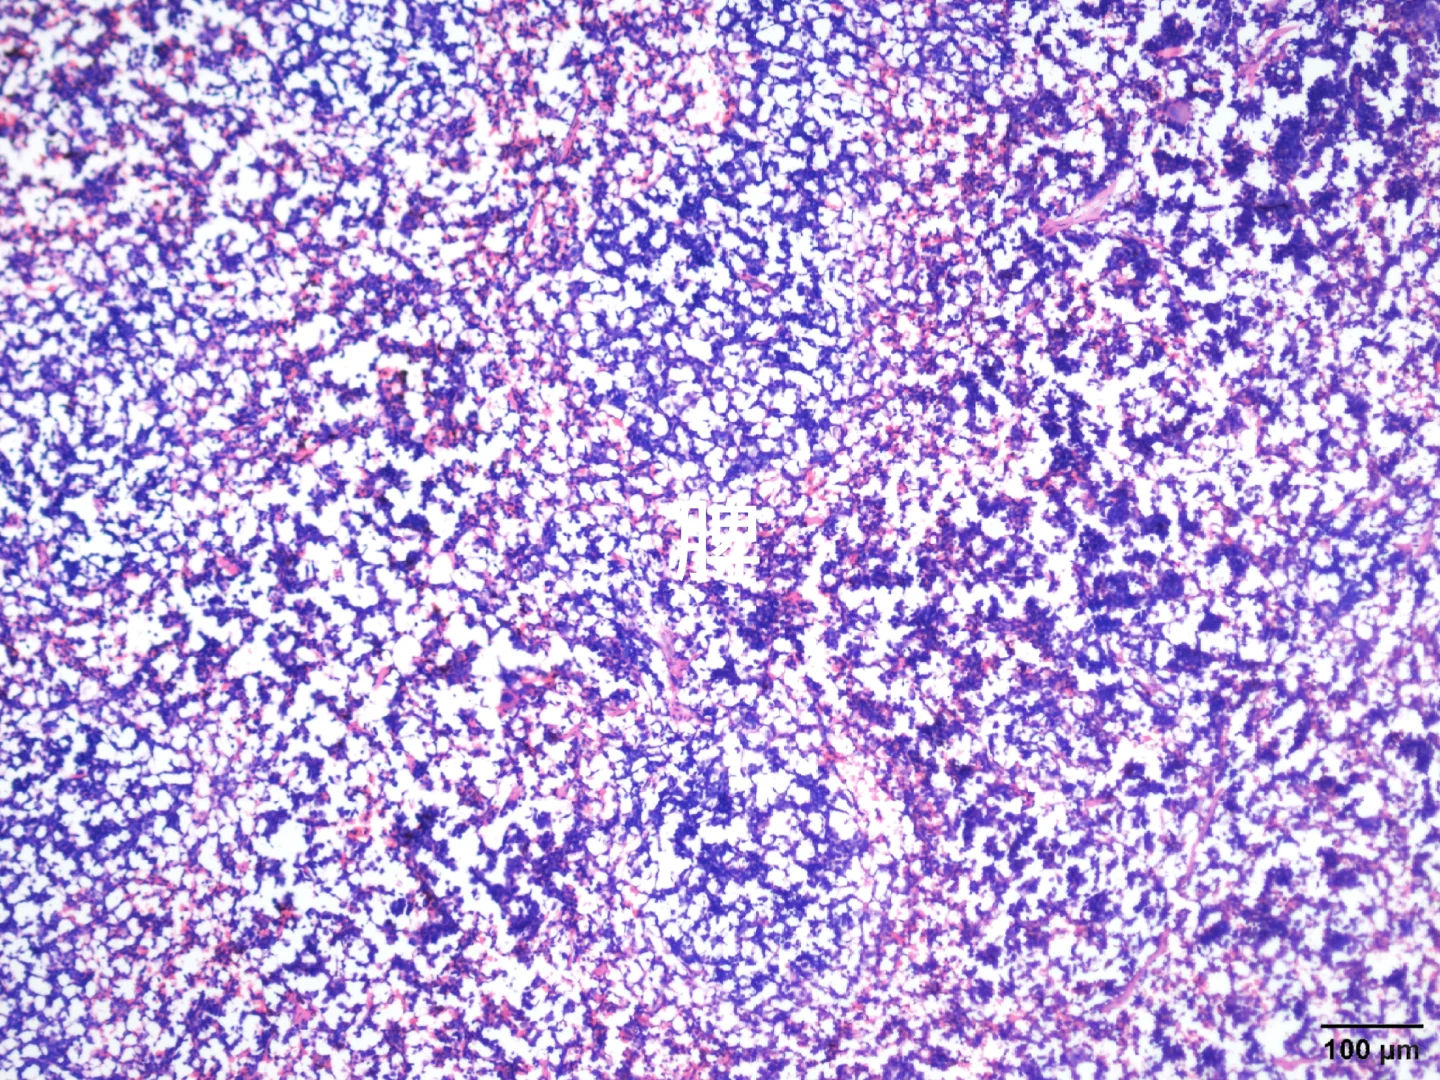

心肝脾肺肾肿瘤HE染色

由于我取了组织后用多聚甲醛固定,然后不小心放-80°一天,后面又放回四度,有没有大神帮忙看看能不能用!